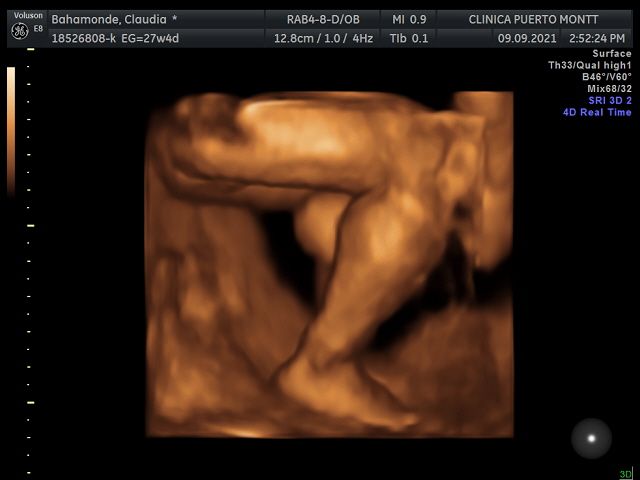

Ecografia volumétrica (3 D y 4D)

Ecografía 4D 90000 $

Muy buen doctor super recomendable, describe todo de manera detallada y se da todo el tiempo para observar bien al bebé

Excelente.. Pude ver a mi bebé a detalle y el doctor se preocupó de que podamos ver su rostro y de saber su sexo con claridad, se preocupó que todo estuviera bien con nuestro bebé lo revisó completamente y me dejó demasiado contenta sin duda recomendado para todas aquellas embarazadas que quieran tener fotitos de su bebé de recuerdo de cuando estuvieron en la pansita

Excelente médico y las ecografías son super detalladas y específicas, muy buenas tomas de la bebe

Excelente atención, la ecografia doppler super genial permite detectar algún problema congénita excelente equipo.

Muy buena la atención y explicación, yo fui por un eco y quedé muy satisfecha y feliz al ver a mi bebé. Excelente profesional.